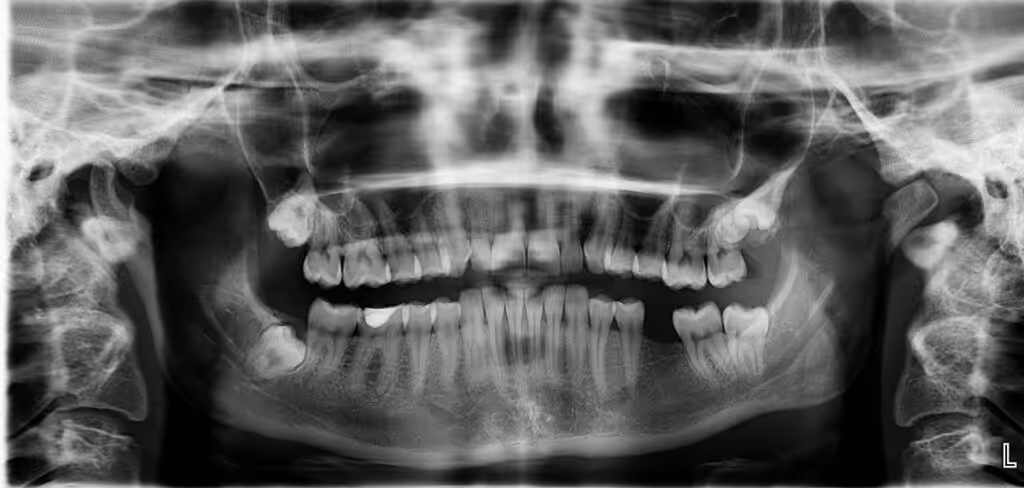

Eine Zahnärztin packt aus!